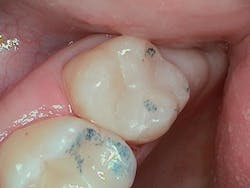

In this case, conservative caries removal allowed the clinician to maximize bond strength while minimizing pulpal trauma and reduce the risk of exposure in a vital asymptomatic tooth.

Clearfil Majesty ES-2 Universal composite (Kuraray Noritake) was selected as the restorative material. It provides easy adaptation due to its creamy consistency that prevents adherence to instruments. This composite material maintains its shape and contours prior to curing, allowing the clinician to create anatomy during placement. As this composite is a universal shade, it allows theSelective-etch technique was employed on the exposed and uncut enamel, followed by an application of Clearfil SE Protect Primer and Clearfil SE Bond. The bonding agent was lightly thinned with air and cured. The composite was placed along the dentin and proximal box margins to achieve a seal around the matrix band.